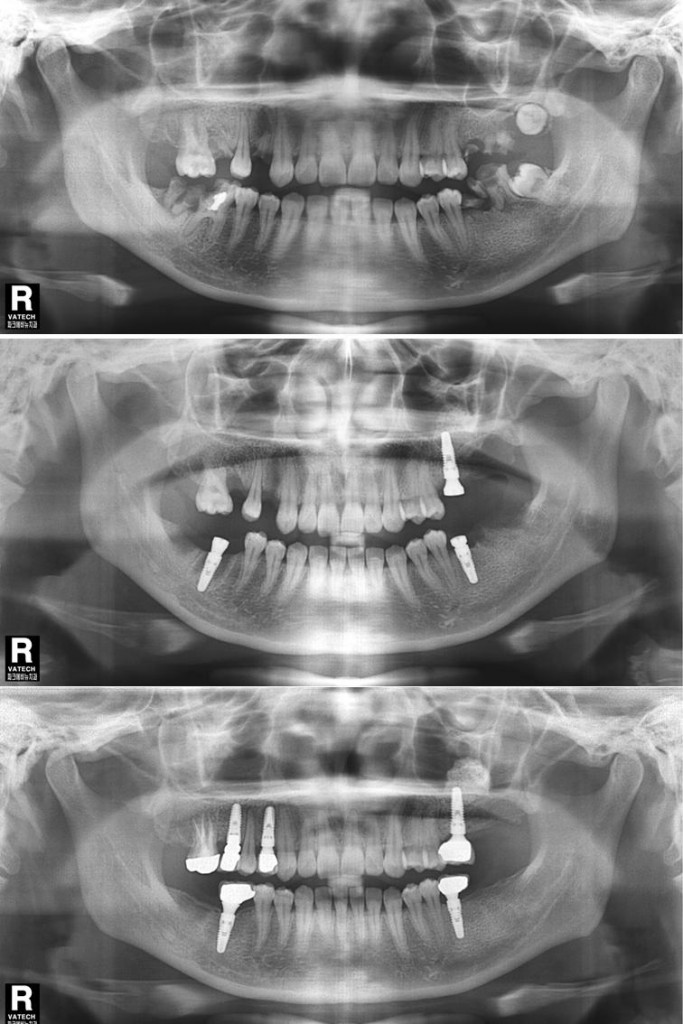

상악동거상술 이식술 뼈이식수술 치료전후 비교사진

상악동거상술